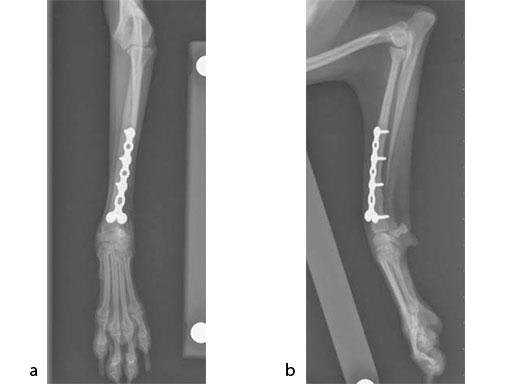

The patient was an approximately 2-year-old 1.5 kg miniature poodle with a radius and ulna fracture of the left thoracic limb. Although there are (1.5 mm screw) cuttable plates available for these small breeds, they require disruption of the periosteum and sometimes the distal fragment has room for only one screw if a straight plate is used. The tiny T plates, using cortex screws, are often too short; ideally at least 3550% of the limb length has to be spanned. In traditional plates, every hole must be filled and contributes to stress protection of the bone. These plate options also do not permit the use of locking screws. Therefore, the condylar LCP 1.5 was a perfect plate for these fractures (Fig 7).

An open but do not touch approach was performed with 3 proximal screws and 2 distal locking screws inserted in the LCP (Fig 8).

After 3 months, the previous fracture of the radius was no longer visible and there was smooth callus in the region of the previous fracture (Fig 9). There was bone loss at the distal ulna, most likely due to stress shielding. Plate removal can be considered at 6 months if bone resorption is a concern.